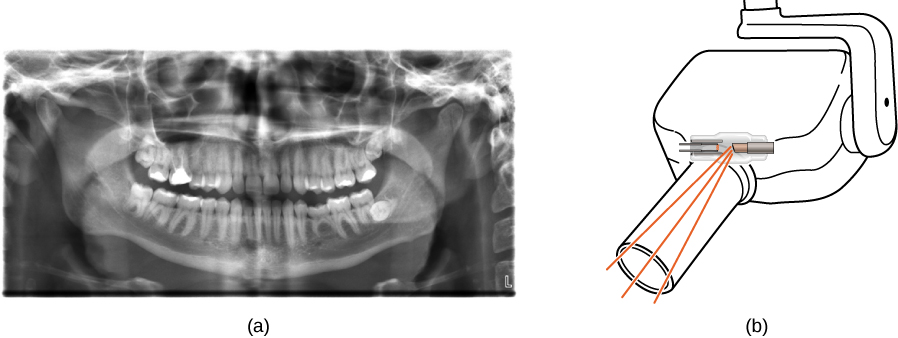

Figure (a) shows an X-ray image of front view of the jaw, especially the teeth. Figure (b) shows a drawing of an dental x ray machine.

Figure 8.25 (a) An X-ray image of a person’s teeth. (b) A typical X-ray machine in a dentist’s office produces relatively low-energy radiation to minimize patient exposure. (credit a: modification of work by “Dmitry G”/Wikimedia Commons)

X-ray Technology

X-rays have many applications, such as in medical diagnostics (Figure 8.25), inspection of luggage at airports (Figure 8.26), and even detection of cracks in crucial aircraft components. The most common X-ray images are due to shadows. Because X-ray photons have high energy, they penetrate materials that are opaque to visible light. The more energy an X-ray photon has, the more material it penetrates. The depth of penetration is related to the density of the material, as well as to the energy of the photon. The denser the material, the fewer X-ray photons get through and the darker the shadow. X-rays are effective at identifying bone breaks and tumors; however, overexposure to X-rays can damage cells in biological organisms.